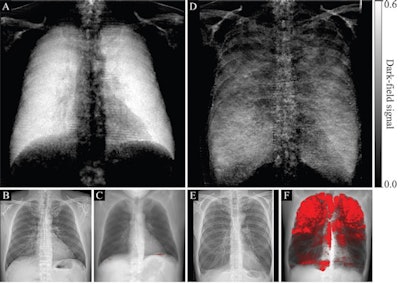

(A, D) Dark-field radiographs, (B, E) attenuation-based radiographs, and (C, F) projections of CT-based emphysema quantification in a healthy 33-year-old man with an emphysema index of 0.1% (A-C) and a 65-year-old man with an emphysema index of 26% (D-F). The same window settings were applied within the respective modality. In B, no abnormalities are apparent. In E, flattened hemidiaphragms and an irregular area of radiolucency are visible. While the dark-field chest radiograph of the healthy subject with no emphysema in the CT-based emphysema projection exhibits a strong homogeneous dark-field signal, the dark-field signal intensity of the subject with pulmonary emphysema appears decreased overall and exhibits an inhomogeneous patchy pattern, corresponding well to the emphysema intensity in the CT-based projection (red overlay, F). Image courtesy of Radiology.

(A, D) Dark-field radiographs, (B, E) attenuation-based radiographs, and (C, F) projections of CT-based emphysema quantification in a healthy 33-year-old man with an emphysema index of 0.1% (A-C) and a 65-year-old man with an emphysema index of 26% (D-F). The same window settings were applied within the respective modality. In B, no abnormalities are apparent. In E, flattened hemidiaphragms and an irregular area of radiolucency are visible. While the dark-field chest radiograph of the healthy subject with no emphysema in the CT-based emphysema projection exhibits a strong homogeneous dark-field signal, the dark-field signal intensity of the subject with pulmonary emphysema appears decreased overall and exhibits an inhomogeneous patchy pattern, corresponding well to the emphysema intensity in the CT-based projection (red overlay, F). Image courtesy of Radiology.The researchers found that locations of focal signal intensity loss on dark-field images corresponded well with emphysematous areas found on CT images. The quantitative analysis showed the dark-field coefficient was negatively correlated with the CT-based emphysema index for all participants (r = -0.54; p < 0.001), the group wrote.